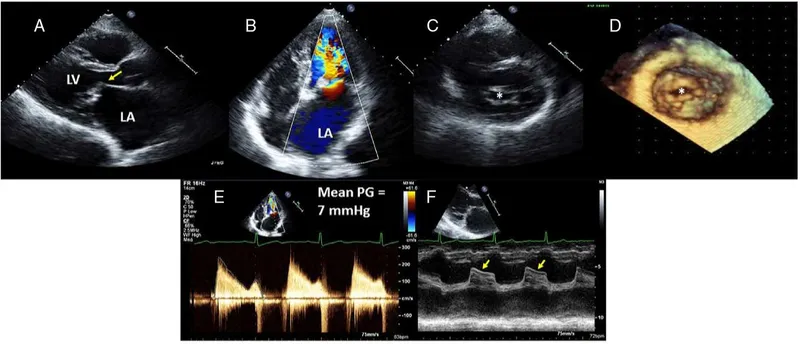

- Echocardiography: Key for diagnosis, severity, LV/RV function.

⭐ Echocardiography is the cornerstone for diagnosis, severity assessment, and LV/RV function in VHD, guiding perioperative management.

- Pathophysiology: Obstructed LV inflow → LA pressure ↑ → LA enlargement, Atrial Fibrillation (AF) risk. Leads to pulmonary venous congestion & Pulmonary Hypertension (PHT: $mPAP$ > 20 mmHg). Severe MS: Valve area < 1.0 cm².

- TEE: Crucial intraop monitor for valvular surgery, guiding repair & assessing hemodynamics.